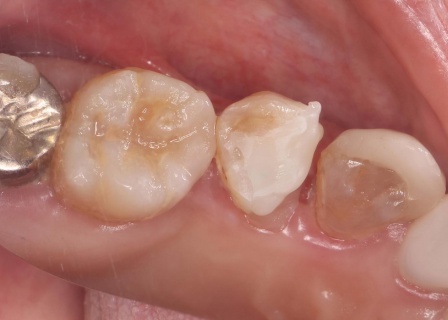

拝見したところ、右上の歯に深い虫歯が見つかりました。

レントゲン撮影で詳しく検査した結果、虫歯が神経まで進行しており、歯根の先に黒い影が確認できます。